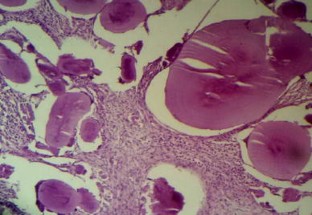

Primary localized amyloidosis in the head and neck region is a rare entity. The most commonly involved organ is larynx. Primary amyloidosis localized to the sinonasal tract is extremely rare. We report one such case along with a brief review of the associated literature. The aim of reporting this case is to emphasize the fact that sometimes nasal amyloidosis can also present with signs and symptoms of nasal and nasopharyngeal malignancy. The definitive diagnosis in such cases depends upon histopathology and further confirmed by immunohistochemistry. A 55-year old male presented with recurrent episodes of nasal bleed, bilateral nasal obstruction, and bilateral hearing loss from last 7 years. On clinical examination a mass was found in the nasal cavity on both sides reaching up to the nasopharynx. Contrast enhanced CT scan revealed that the mass was extending up to the skull base and destroying bony landmarks of the nasal cavity and paranasal sinuses. Mass was proved to be amyloidosis after histopathological examination. It showed multiple blotches of globular submucosal deposit of amyloid, on staining with Congo red. Immunohistochemistry confirmed AL amyloidosis with expression of mixed kappa and lambda light chain immunoglobulin (κ > λ). No evidence of systemic amyloidosis was found after proper work up. It was managed by conservative surgery.